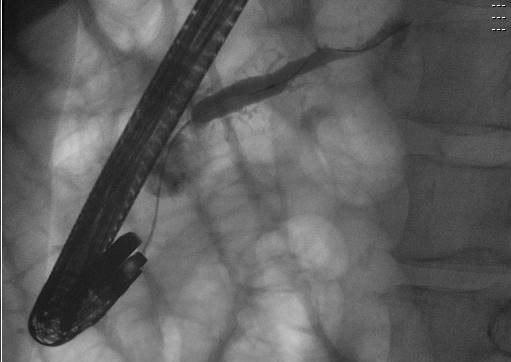

@IUGastro Advance Endoscopy (AE) and @RileyChildrens frequently collaborate, giving our AE fellow a unique opportunity to be part of pediatric ERCP cases. One of many ways @IUGastro and @RileyKids help train our next-generation therapeutic endoscopists. @MunishAshatMD @studabaka

English

#TakeoverTuesday With world-renowned faculty

@IUGastro @ Advance Endoscopy (AE) Training is one of the best in the country.

Dr. Stuart Sherman @studabaka and @MunishAshatMD

(AE Fellow) successfully treating a pancreatic duct disconnection with PD stenting.